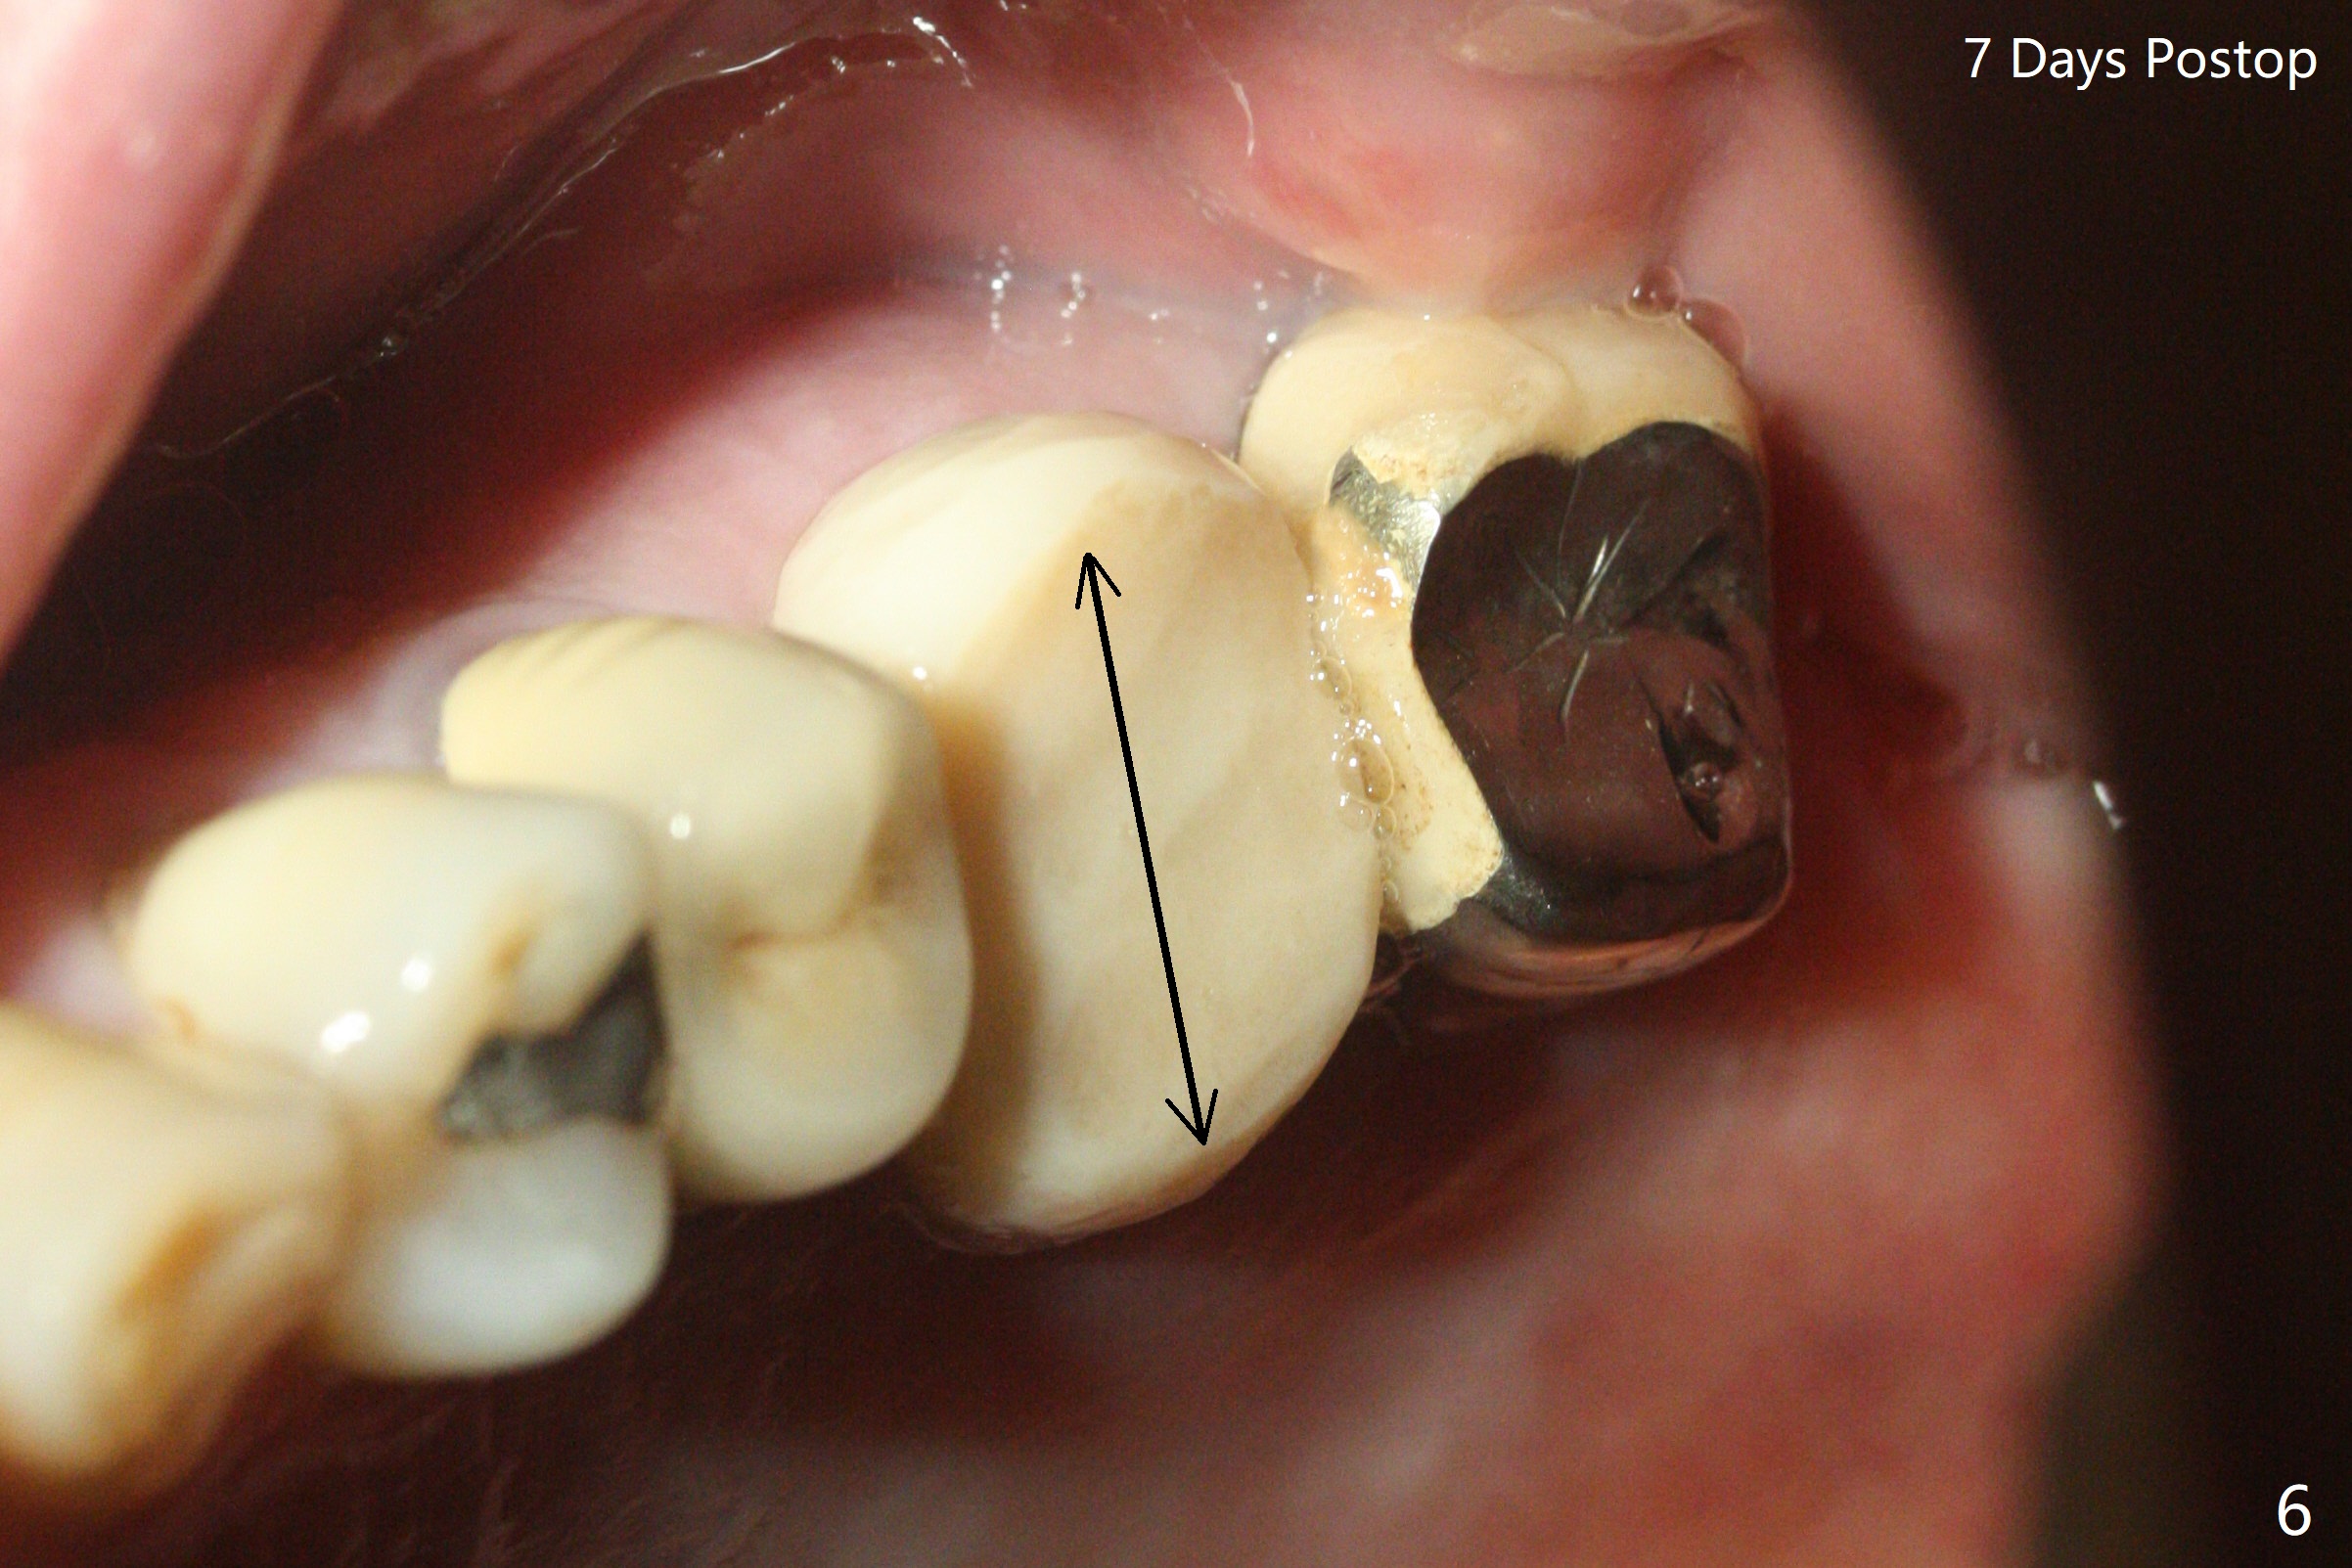

左上6腭侧退缩牙龈(图一:箭头)深部没有骨壁(图二:*),4.5x11毫米植体周围缺损(图三:*)由粘性骨粉(皮质骨,图四:*)填入,即刻临时牙冠(图五:P)覆盖腭侧缺损(空箭头)和PRF膜。临时牙冠颊腭侧做的很宽(图六),目的是关闭腭侧缺损,术后四周在不影响骨粉覆盖情况下,牙冠腭侧适当向颊侧缩小(图七:箭头),但是不应该缩短龈下边缘。术后四个月骨粉形态接近原位骨(图八),但是腭侧软硬组织仍有缺损,炎症。